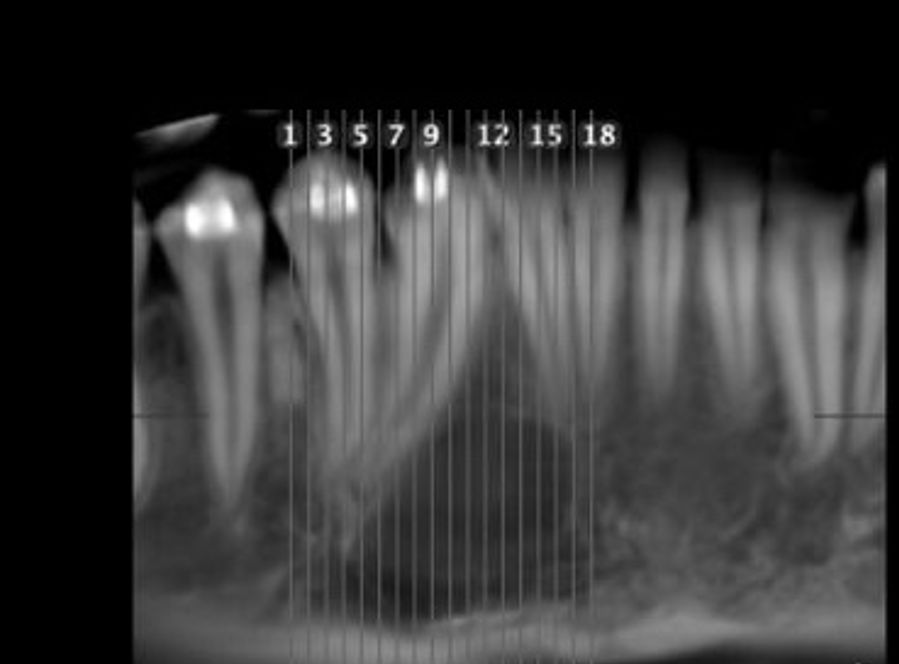

11-year-old boy with a large mass

An 11-year-old boy with a large mass over the right anterior maxilla.